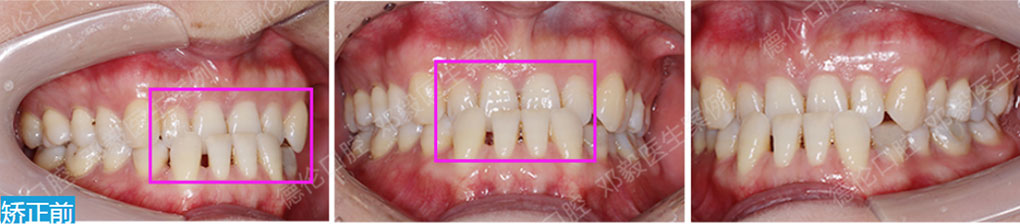

- 【診斷】

骨性Ⅱ類高角伴擁擠

上頜前突、下頜后縮、下前牙唇傾

下中線右偏2.5mm,21 35°扭轉(zhuǎn)13低位

打造醫(yī)生:德倫口腔正畸中心熊小琴主任

- 【治療方案】

拔除3顆多余的咬合不正的智齒,通過(guò)支抗釘控制

失狀向和垂直向,推上、下牙遠(yuǎn)移解決擁擠改善前

突,使整個(gè)頜平面逆時(shí)針旋轉(zhuǎn),改善了下頜后縮的

情況

矯治前后對(duì)比

牙列整平排齊,前牙內(nèi)收;覆蓋、覆合正常;尖牙和磨牙達(dá)到中性關(guān)系;上下中線對(duì)齊;下頜后縮改善